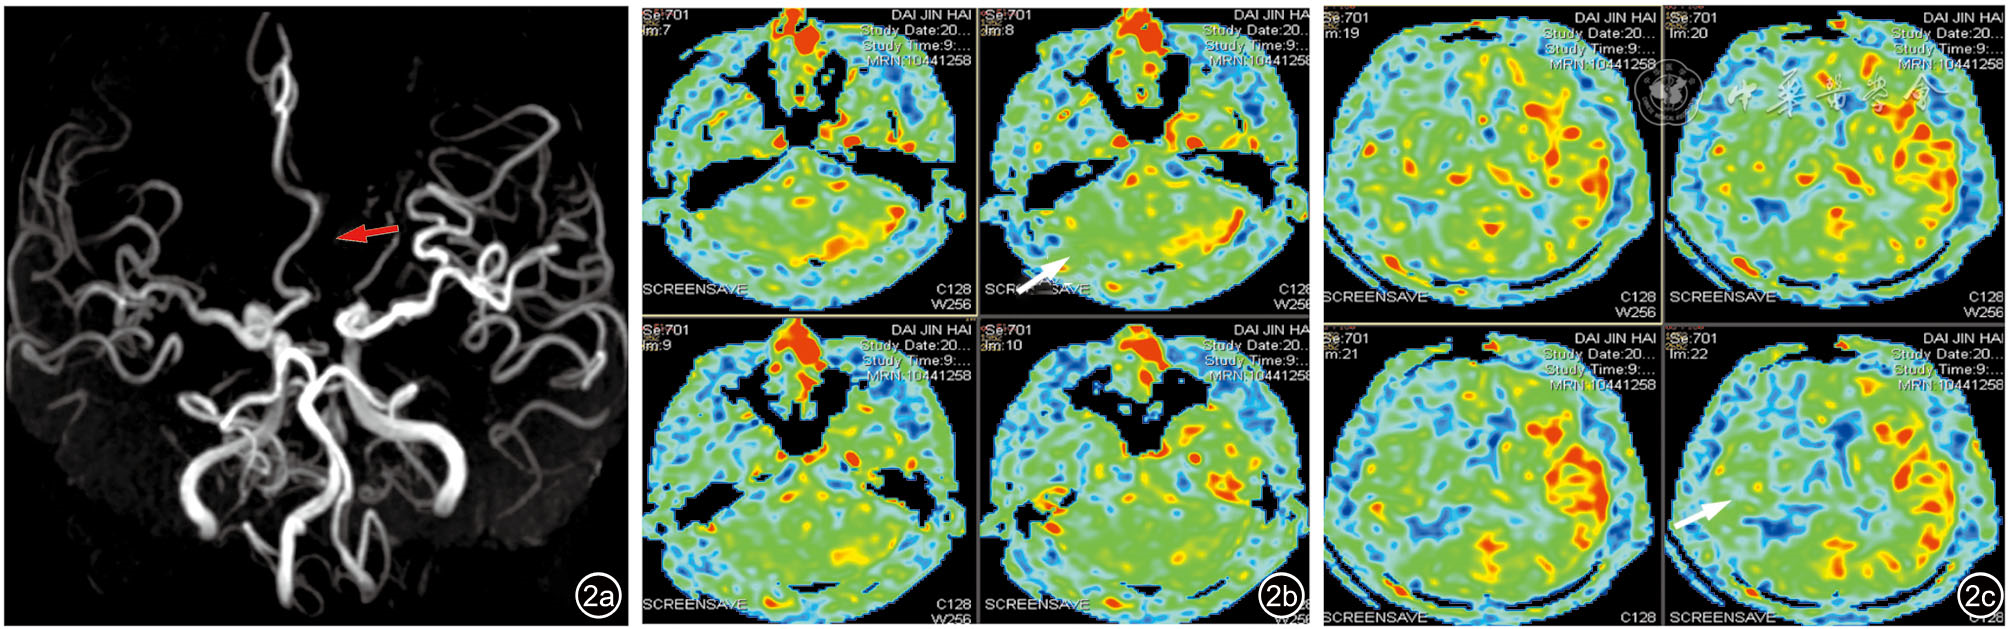

图2 术前患者的头颅一站式磁共振血管成像-动脉自旋标记(MRA-ASL)序列影像。图a为MRA序列,红色箭头所示左侧大脑前动脉未显影;图b为术前患者的ASL序列,白色箭头所示右侧小脑及脑干区域脑血流量(CBF)对比左侧小脑灌注呈下降改变;图c为术前患者的ASL序列,白色箭头区域及周围蓝绿色所示右侧大脑半球CBF对比左侧半球灌注呈下降改变